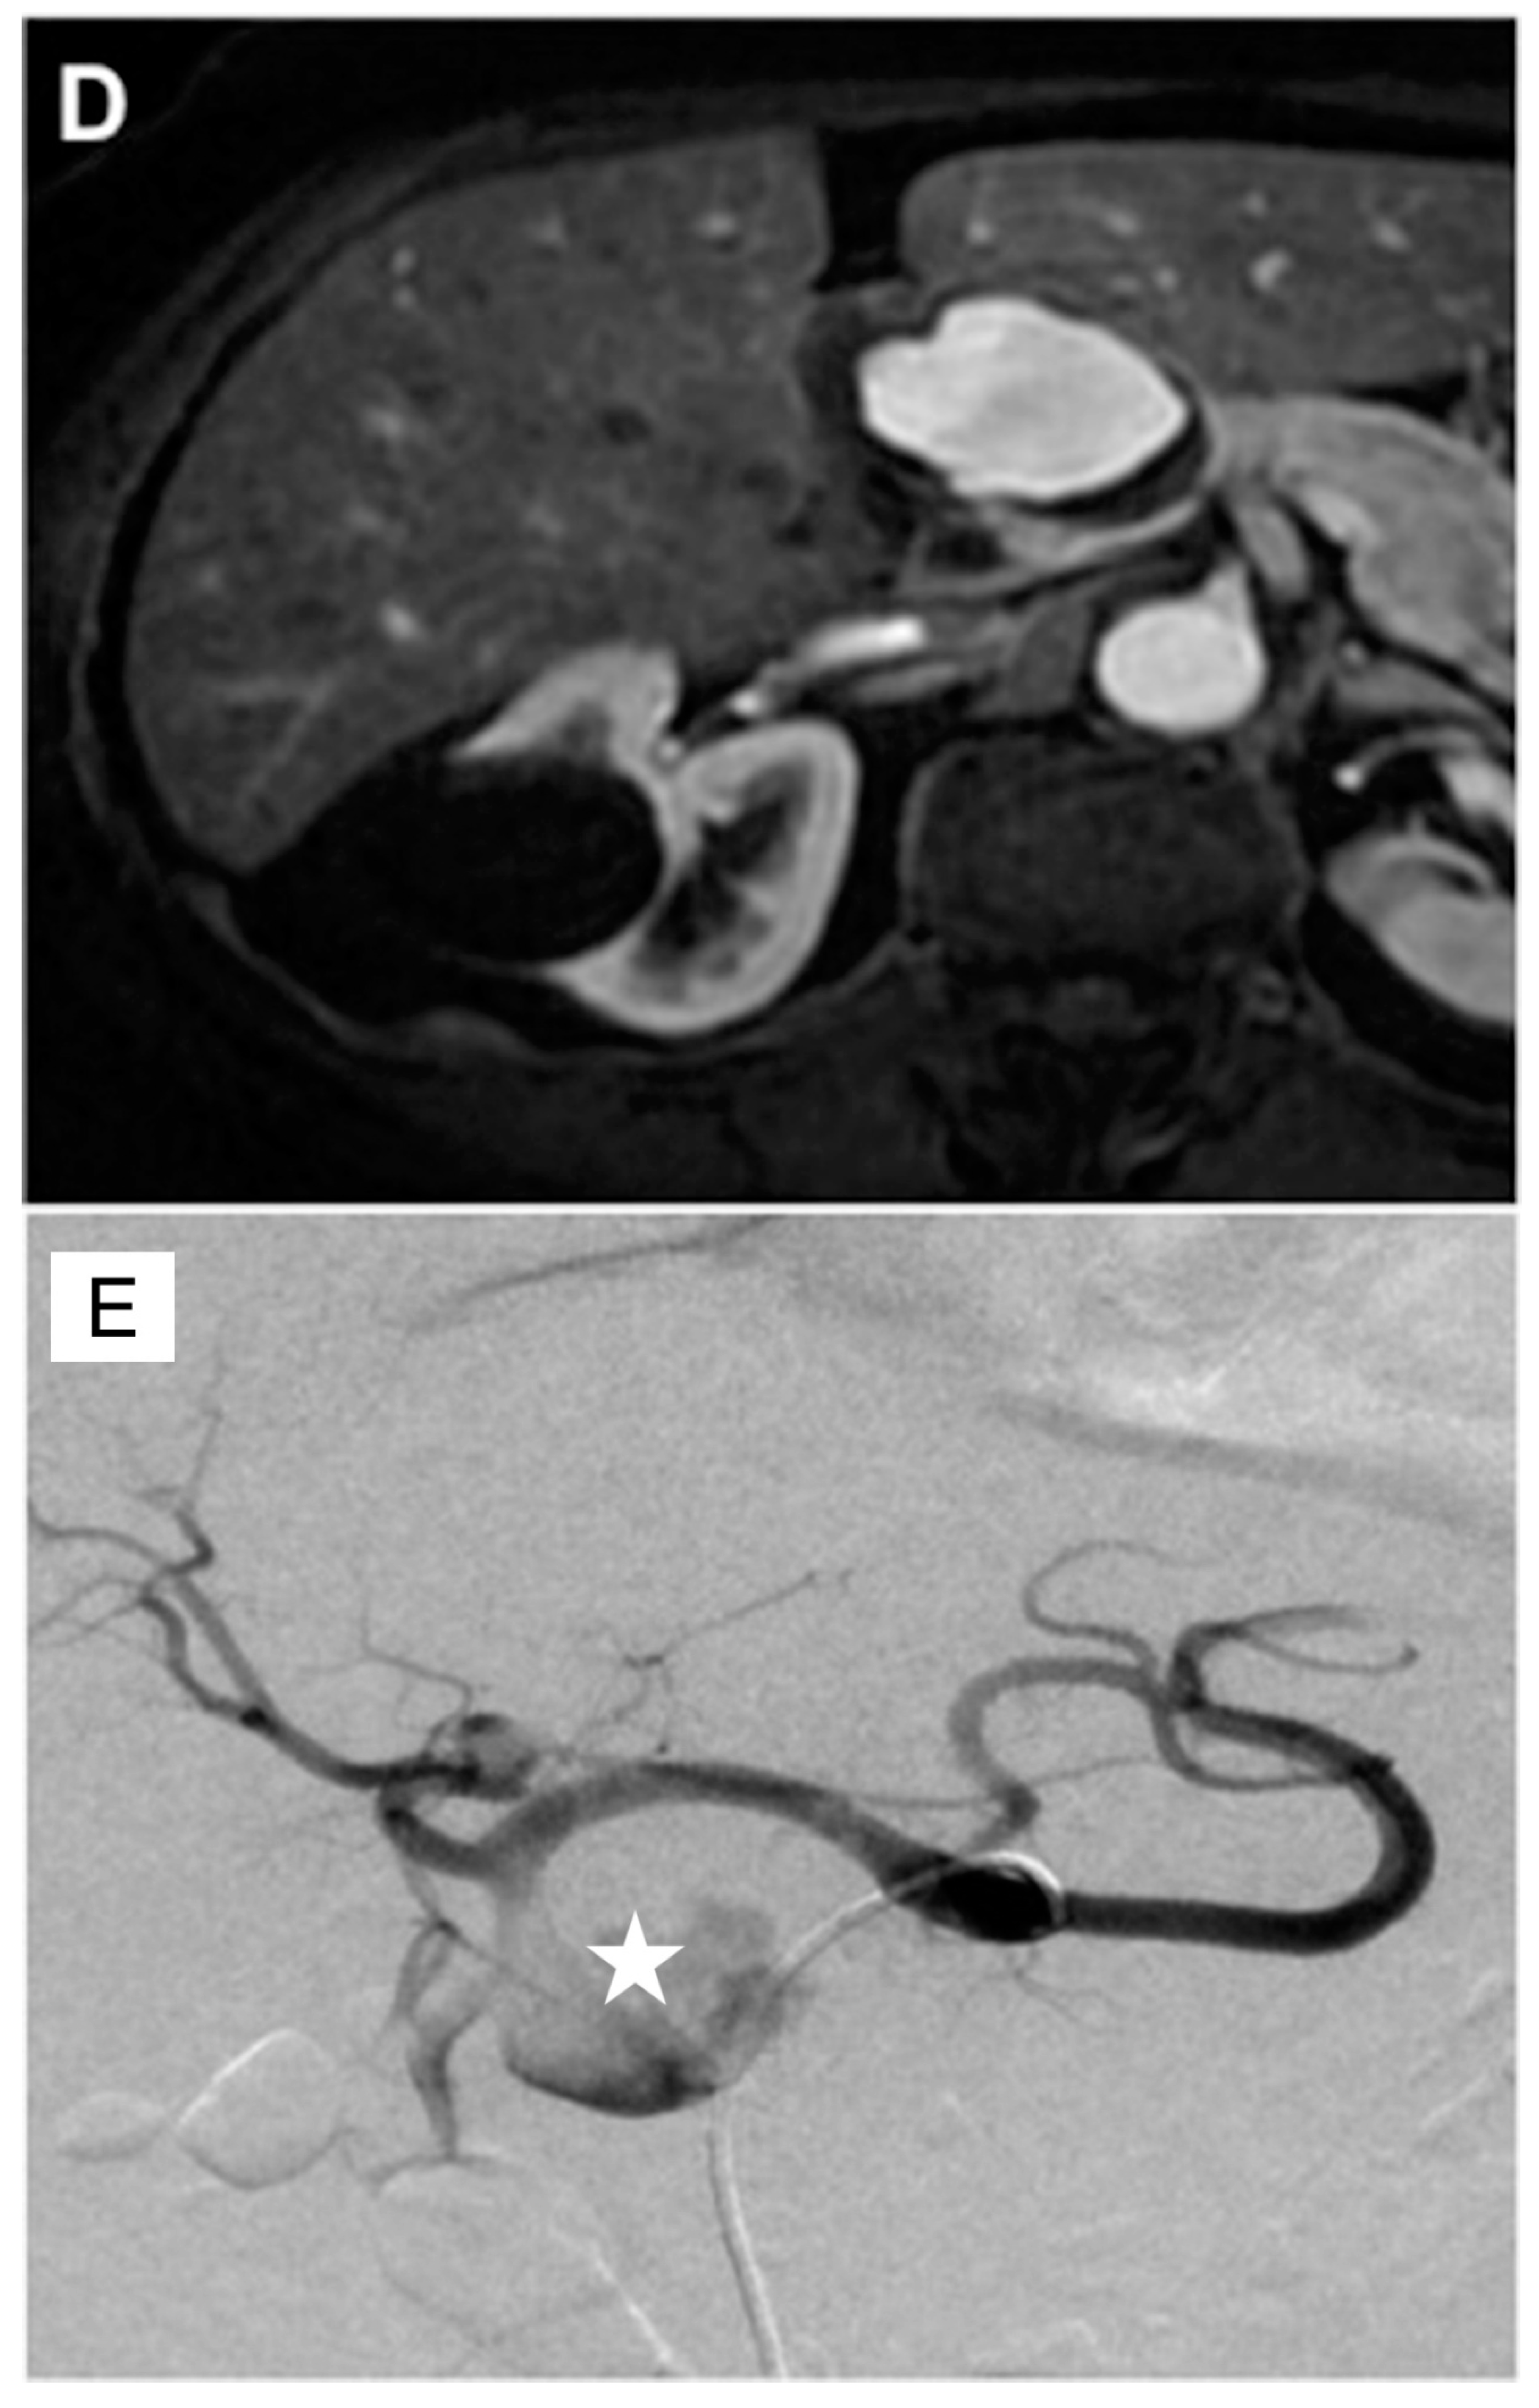

3. GDA Embolization in Gastrointestinal Bleeding

4. GDA Pseudoaneurysm Embolization

5. Pre-Y-90 GDA Embolization